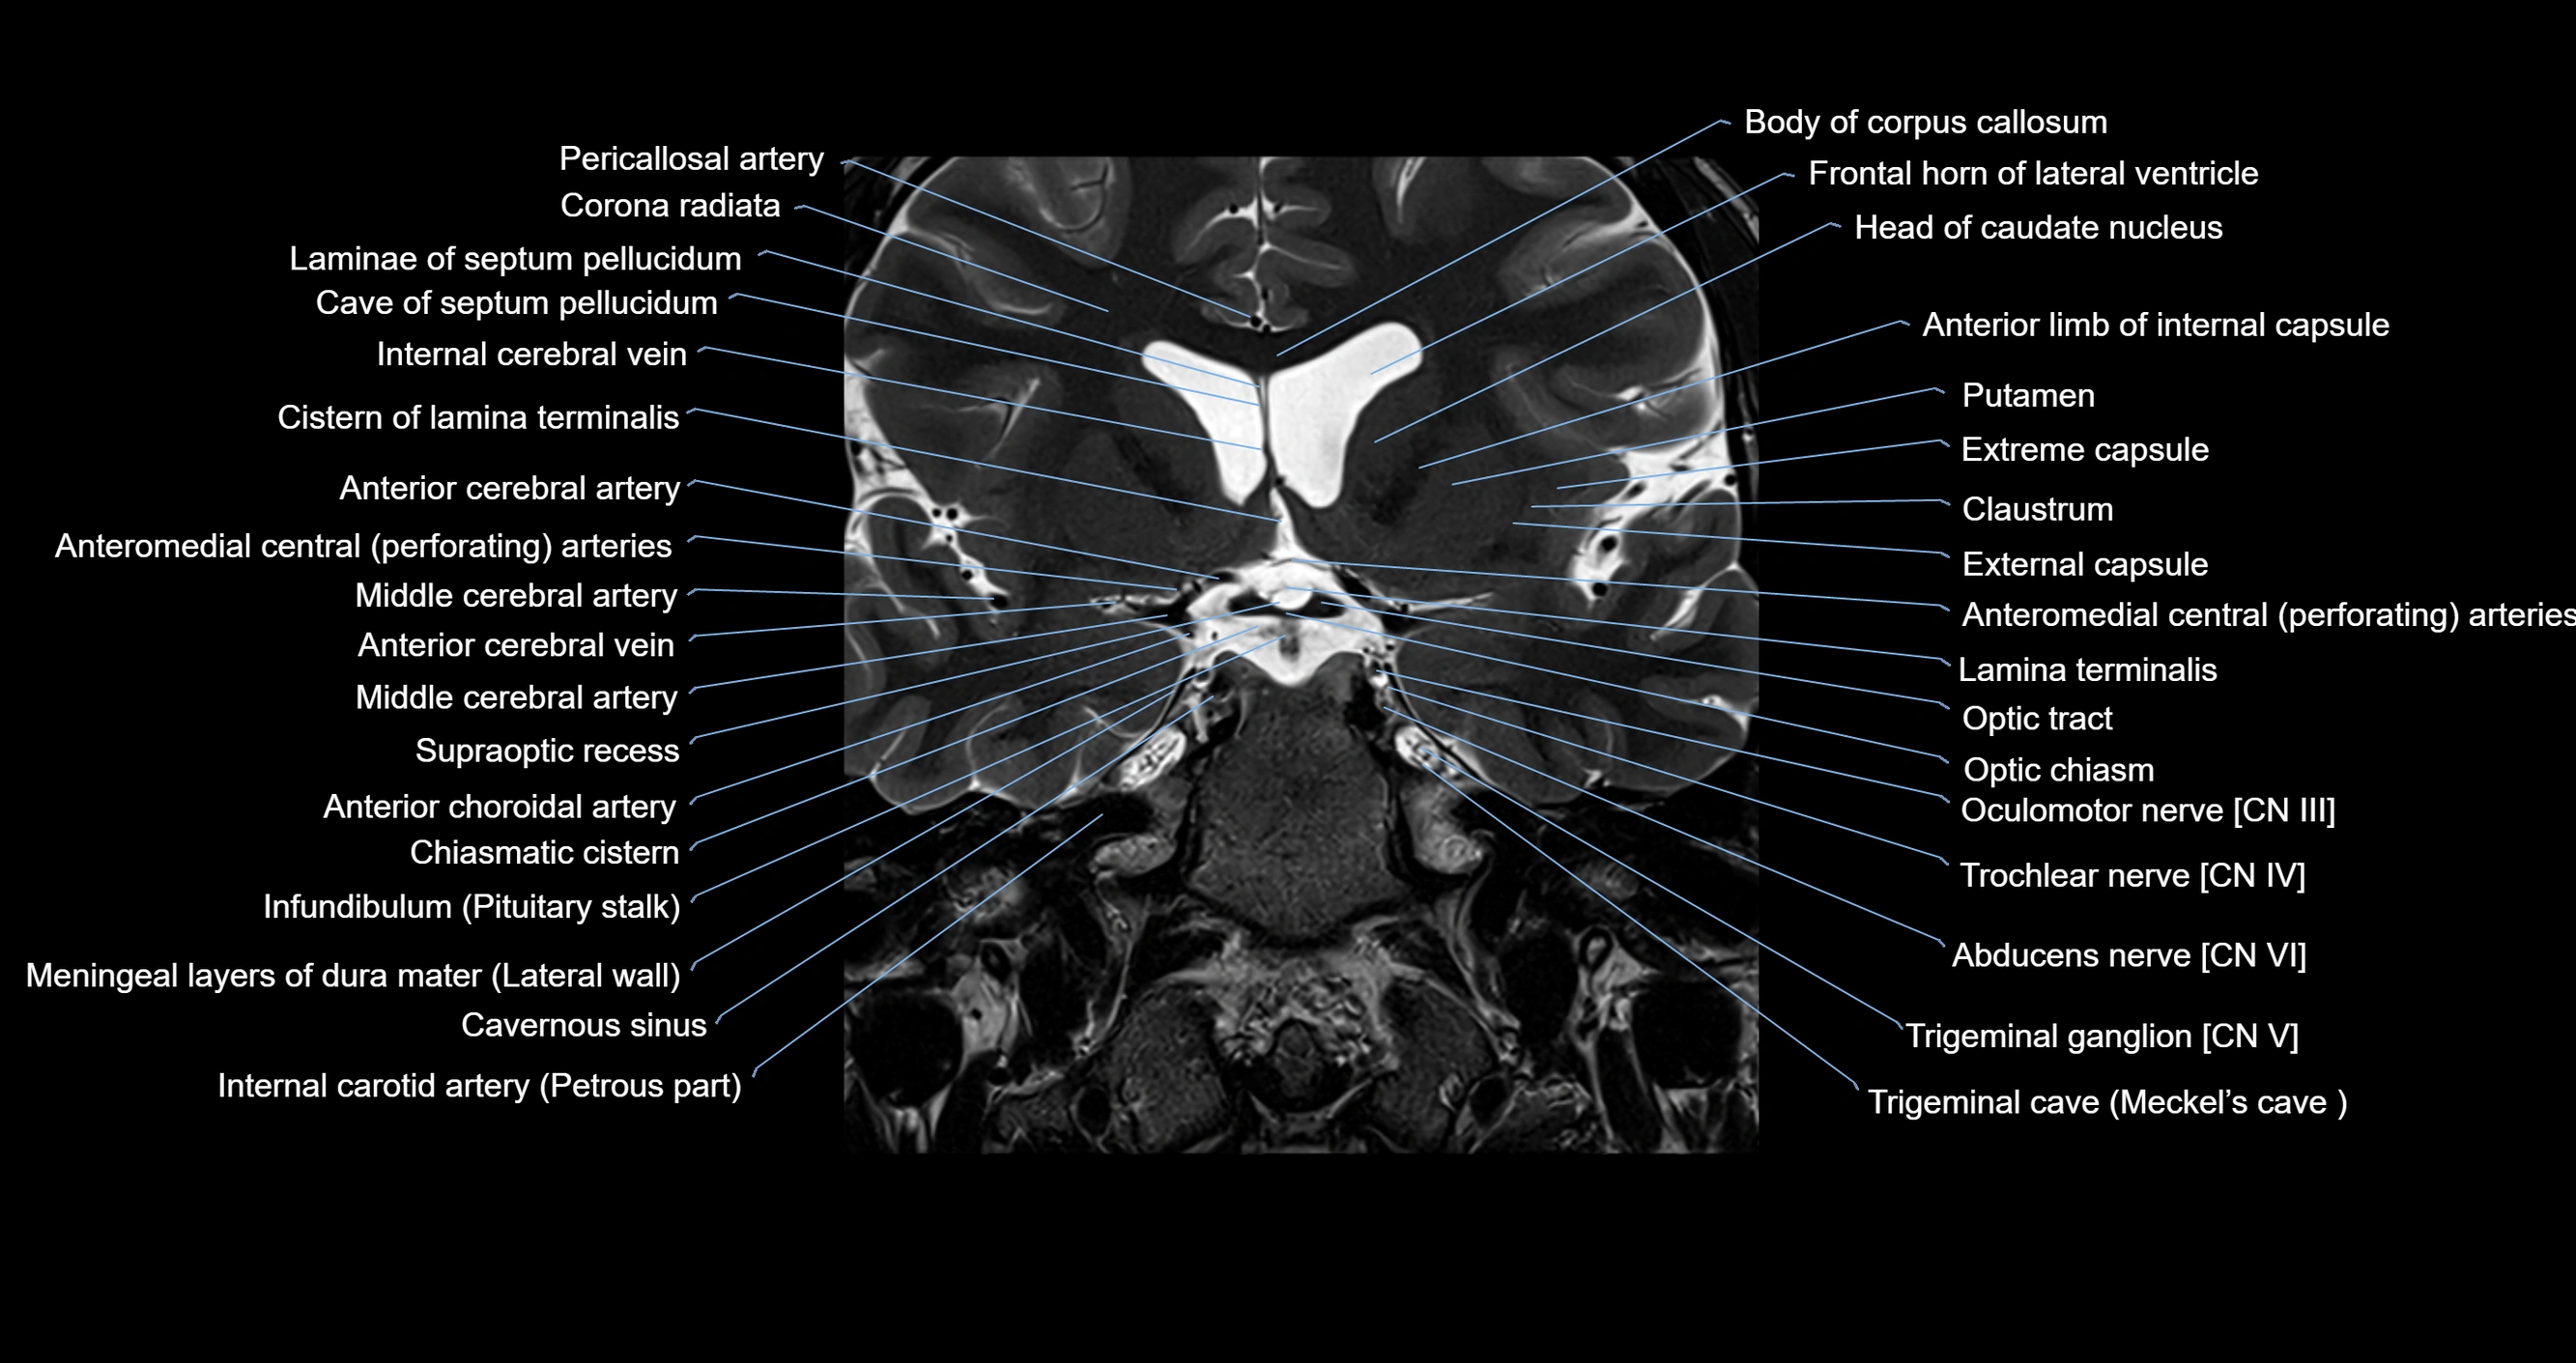

MRI images